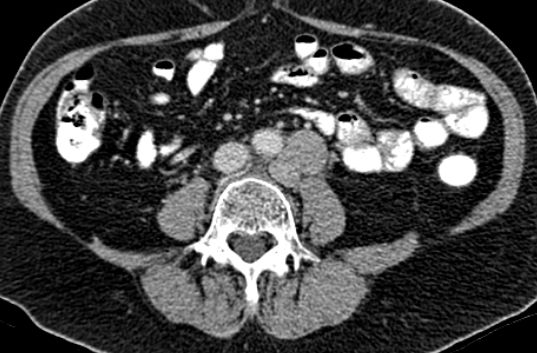

| paraaortale Lymphknoten - Metastasen | 54-jährige Frau, die vor 4 Jahren wegen eines

Zervix - Karzinoms FIGO IIIb mit Radiochemotherapie behandelt wurde. Damals praevesikaler Harnstau beiderseits. Jetzt neu Harnstau links. RF links paraaortal. ![]() | |||

![]() |

![]() | |||